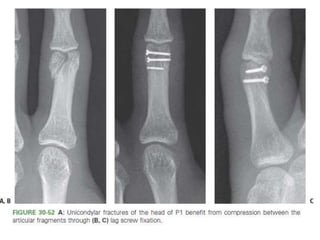

• #85 Figure 30-52 A: Unicondylar fractures of the head of P1 benefit from compression between the articular fragments through (B, C) lag screw fixation.